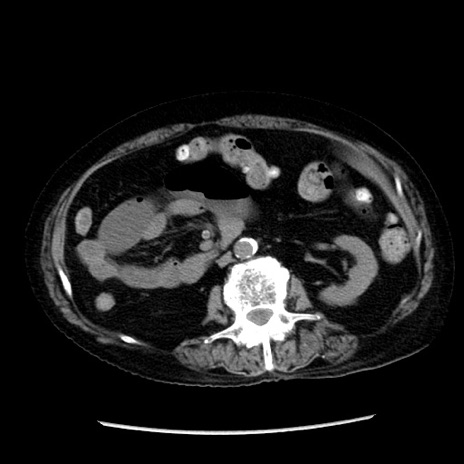

冠状断像

【症例】 90歳代女性

【主訴】 腹痛・嘔吐

【現病歴】今朝から左側腹部痛を認めた。 経過観察していたが、嘔吐を認めたため来院。

【既往歴】 子宮癌術後

【身体所見】 意識清明、BP 127/54mmHg、P 98bpm Sp02 95%(RA)、BT 35.8°C、腹部平坦・軟腸ぜん動音聴取良好、右下腹部圧痛(+) 反跳痛なし

【データ】WBC 9800、CRP 0.46